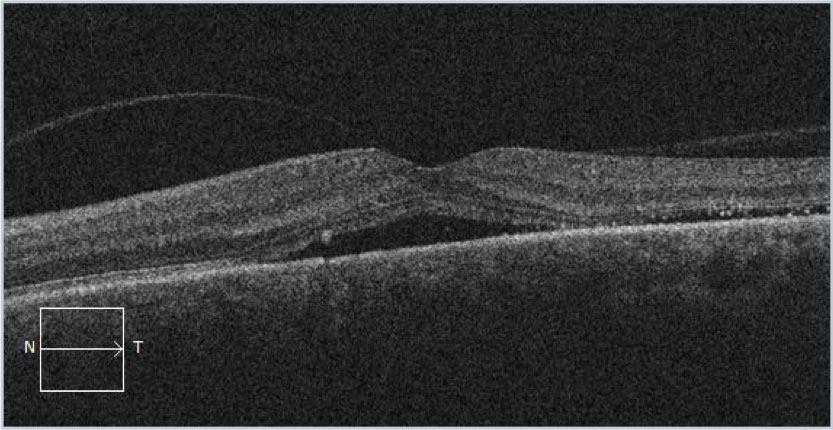

This OCT image is through the foveal center demonstrating subretinal fluid. This image is a useful reminder as to the importance of a good differential diagnosis for subretinal fluid.

The OCT image through the lesion demonstrates bowing of the RPE over the underlying choroidal mass. A small amount of subretinal fluid is also noted. The OCT-Angiogram demonstrates some increased vascularity but in isolation could not be used for diagnostic confirmation.